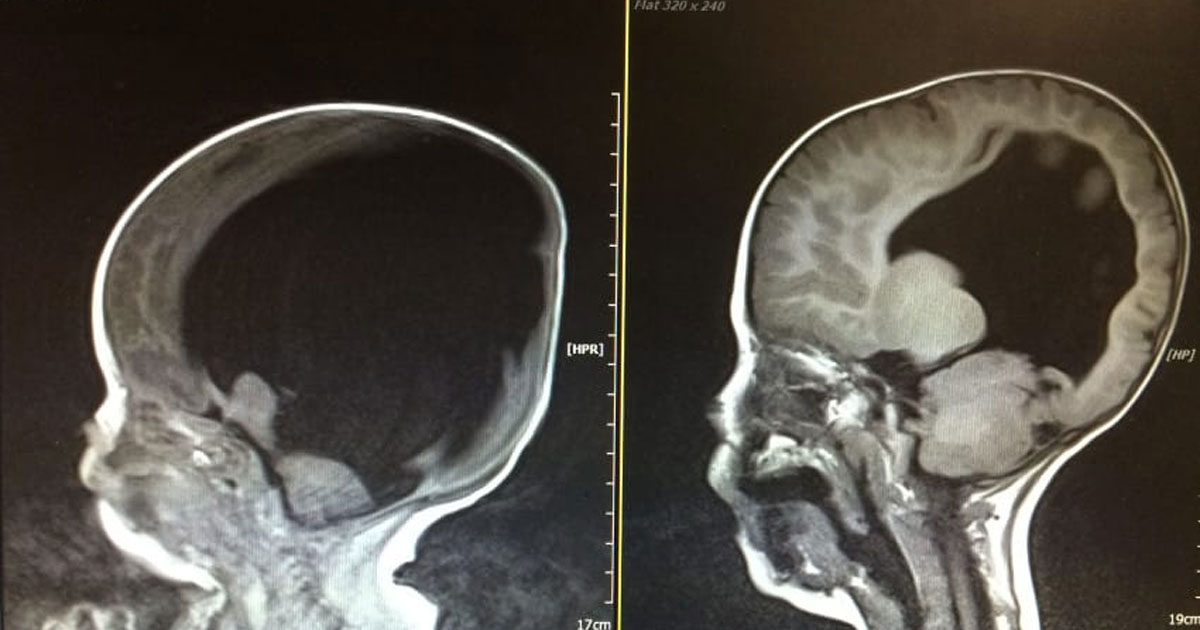

Как и следовало ожидать, Ной родился с 98% нефункционального мозга, в результате повреждения жидкости гидроцефалии. Но то, что произошло дальше, было чудом. Несмотря на, казалось бы, необратимое состояние, мозг Ноя постепенно начал расти.

Процесс развития ребенка занял больше времени, чем у сверстников, но мальчик даже научился говорить и старался догнать своих одногодок. В то время, как он все еще сталкивается с экстремальными осложнениями со здоровьем, в результате расщелины позвоночника, случай Ноя является одним на миллион, которая будет исследоваться. BBC решило снять документальный фильм о невероятном восстановления малыша.